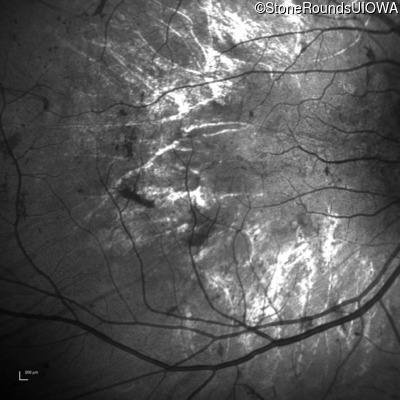

Infrared Fundus Photograph - Left - 5/160

Exemplar